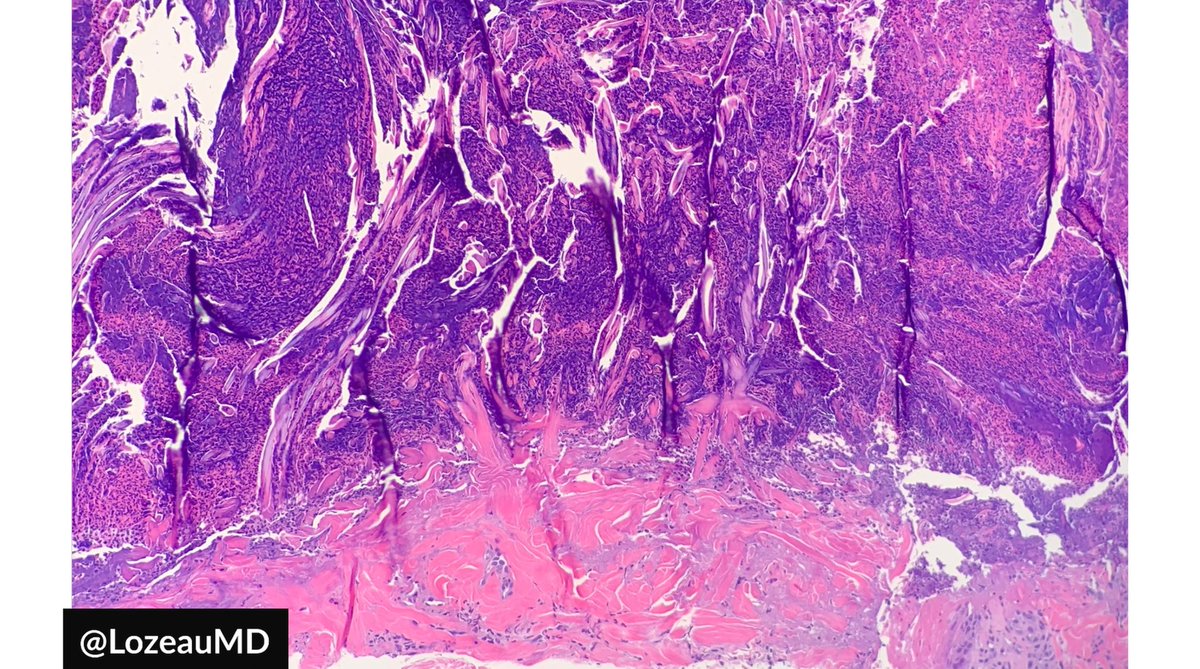

This EIC really puts the "inclusion" in epidermal inclusion cyst. These are often submitted as "sebaceous cysts."

#pathology#dermpath#Dermatology pic.twitter.com/Ld0zBJIumf